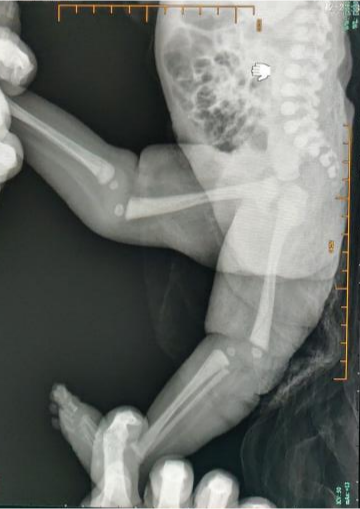

骏骏,2岁3月,出生后发现双下肢结构异常,在当地医院诊断为“先天性多关节挛缩症”、“先天性双膝关节反曲畸形”、“先天性双踝关节脱位”、“先天性双手指屈曲畸形”。 出生后骏骏在当地医院进行多次石膏固定及牵引治疗,症状有所改善。但随着生长发育,骏骏双膝关节可伸直并轻度屈曲,但仍无法完成独立日常生活。 2021年5月吴江区儿童医院副院长华军携护理部、手术麻醉科、外科的专家们至新疆义诊。他们在新疆乌鲁木齐市妇幼保健院友爱医院院区了解到骏骏的情况后,决定帮助骏骏一家,帮助她完成独立日常生活的梦想。 2021年12月,在多方的协助下,骏骏一家来到了吴江区儿童医院进行手术治疗。手术是由总院王晓东教授和吴江院区戴进主任共同完成。考虑到骏骏的家庭困难,治疗费由医院“童心圆”基金会支持。 吴江区儿童医院小儿骨科自建科以来,积极组织和参与各类义诊、志愿者服务活动。在医院“童心圆”儿童慈善救助基金的共同努力下,深入边远贫困地区,已为数位疑难罕见病患儿家庭带去希望。 苏州市吴江区儿童医院(苏州大学附属儿童医院吴江院区)骨科团队目前有小儿骨科专科医师8名,其中高级职称医师1名,中级职称医师2名;博士研究生2名,硕士研究生6名。团队积极依托苏州大学及附属儿童医院平台积极开展各类小儿骨科医疗技术,包括各类儿童骨折的微创治疗及肢体畸形的个体化矫正,其中一些项目,如儿童骨囊肿的微创穿刺注射治疗、成骨不全的治疗等,在苏南地区率先开展,在江苏享有一定的知名度和影响力。 门诊时间 骨科专家门诊: 戴 进 主任医师 出诊时间:上午:周二、四、六 朱伦庆 副主任医师 出诊时间:上午:周日 骨科专科门诊:每天下午